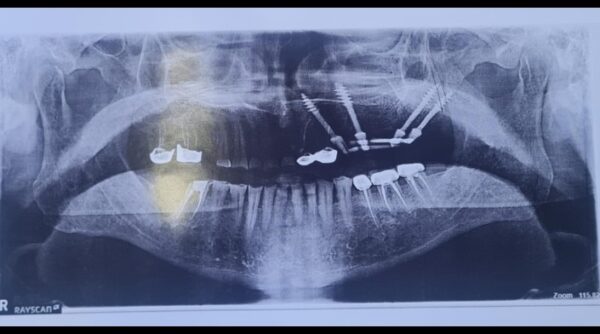

हिमालयन डेंटल सेंटर में दांतों की जांच के लिए डेंटल OPG (ऑर्थोपंतोंमोग्राम) व डिजिटल डेंटल एक्स-रे एवं डिजिटल इंप्रेशन जैसे अति आधुनिक उपकरण उपलब्ध हैं यहां पर सभी प्रकार की दंत चिकित्सा उपलब्ध है ।

उन्होंने बताया कि हिमालय डेंटल में डेंटल OPG (ऑर्थोपैंटोग्राम) और डिजिटल डेंटल एक्स-रे जैसी सुविधाएं भी उपलब्ध हैं। ये उपकरण दांतों और जबड़े की स्थिति का सही मूल्यांकन करने में मदद करते हैं, जिससे डॉक्टर को सटीक निदान करने में सहायता मिलती है। डिजिटल इंप्रेशन तकनीक के द्वारा, मरीज के दांतों का सटीक रूप में आकलन किया जाता है, जिससे इंप्लांट लगाने की प्रक्रिया और भी सरल और सटीक हो जाती है।